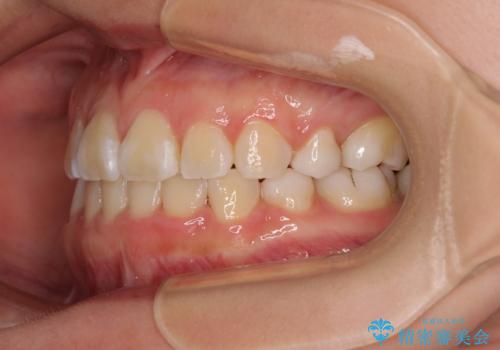

- 内側に生えている歯や埋もれた奥歯を気にして来院された患者様です。

顎の骨が小さいため、歯列が収まりきらずに叢生や未萌出となっている状態でした。

埋もれた奥歯を萌出させ、さらにデコボコを解消するために、上下左右の第1小臼歯4本に加え、親知らず4本も抜歯し、ワイヤー装置にて矯正治療を行うこととしました。

親知らずの抜歯により埋もれた奥歯周辺の歯肉が切除され、矯正装置が装着できるようになりました。

奥歯の移動、特に下顎大臼歯の移動は時間がかかることが多く、3年以上の治療期間を想定していましたが、想像以上に動きがよく、2年強で終えることができました。